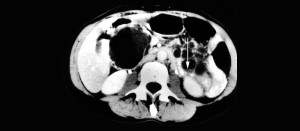

quiste-en-el-pancreas